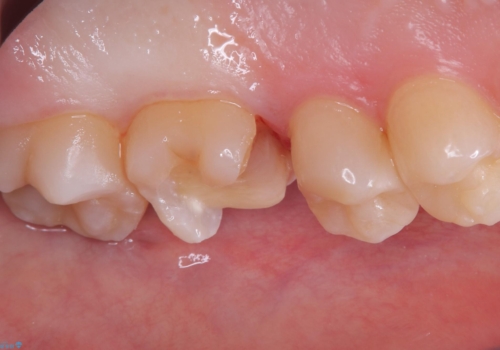

適合性、審美性、材料安定性からセラミックインレーでのやり替えとなりました。う蝕を除去いていくと、残存歯質が薄く破折リスクの高い部位が出てきたため患者さんにも説明し、アンレー窩洞としました。

セラミックアンレー接着時は、ラバーダム防湿を行っています。